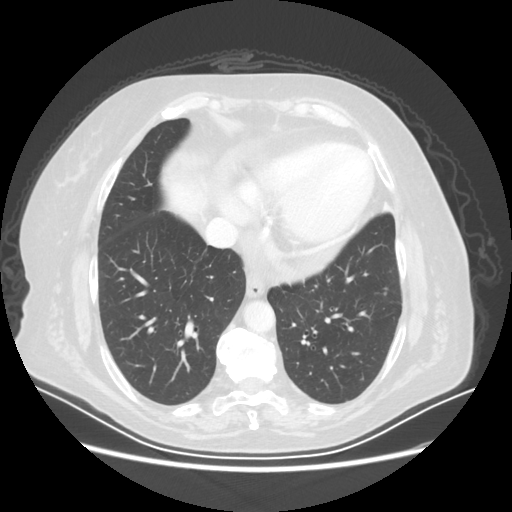

Reconstructed NATIVE CT scan (cycle consistency)

No window - Raw intensity values

Lung window (WL -600, WW 1500 β†’ Low βˆ’1350, High +150)

Mediastinum window (WL 40, WW 400 β†’ Low βˆ’160, High +240)